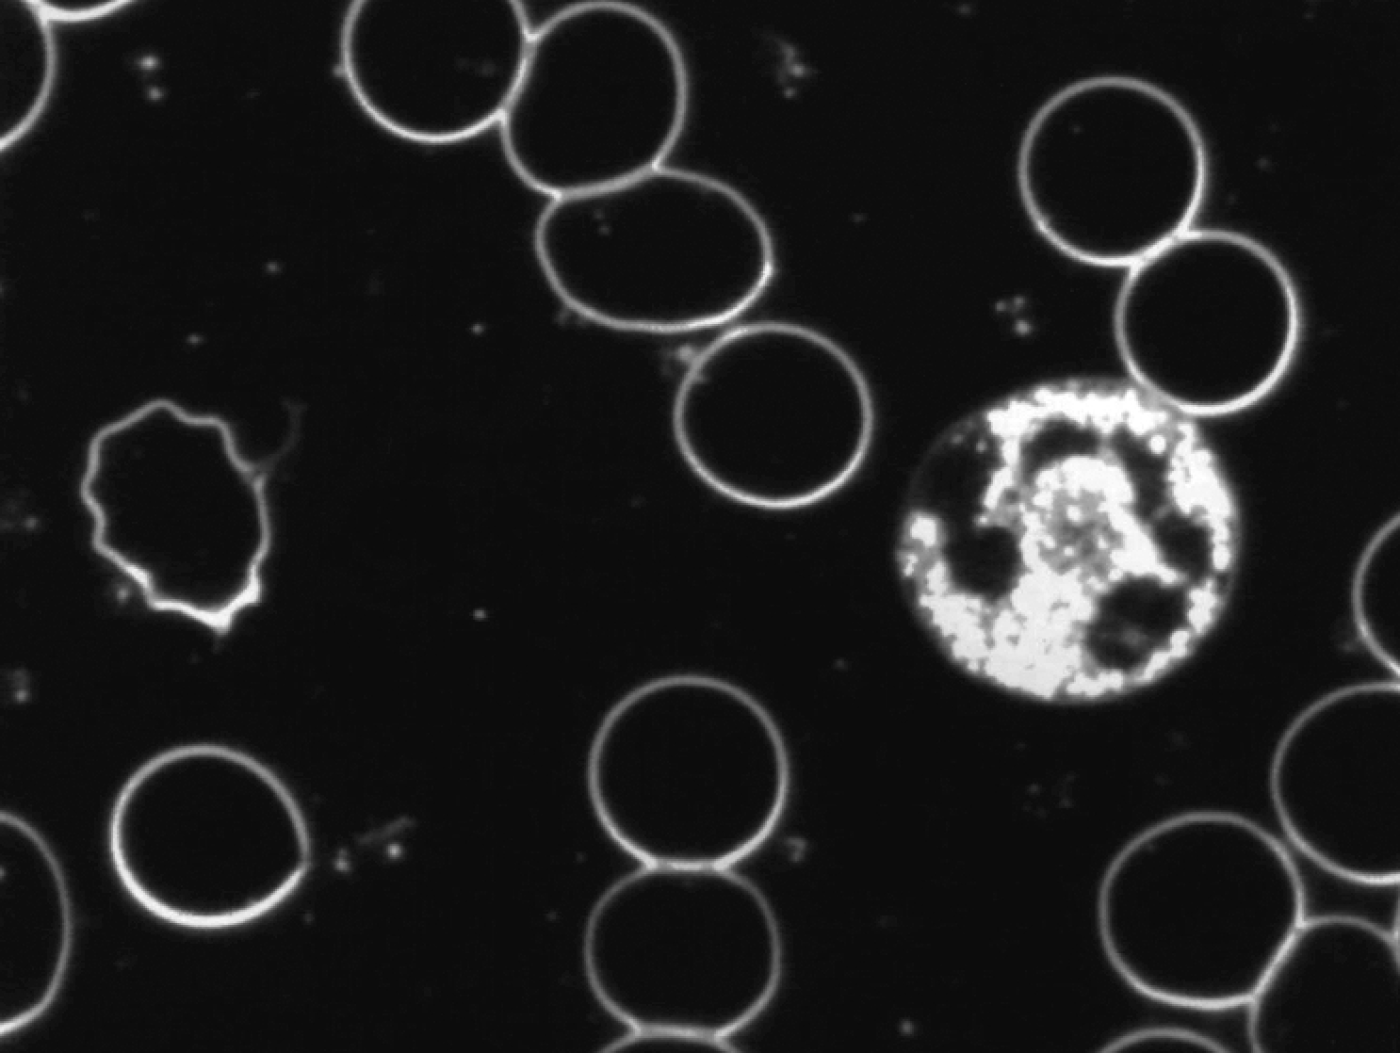

Na de neutralisatie vertonen de witte bloedlichaampjes (granulocyten) een verhoogde motiliteit en de intracellulaire activiteit neemt toe. De vorming van pseudopodieën treedt frequenter op. De witte bloedlichaampjes kunnen dan actief zijn in het afweersysteem.

Zie ook onderstaande foto’s met een karakteristiek beeld van vóór en na de neutralisatie met Benzoliet.

Levend bloedbeeld

vóór neutralisatie met Benzoliet

na neutralisatie met Benzoliet

De veranderingen die we hebben geconstateerd in met name de witte cellen na blootstelling aan technische en geopathische verstorende subtiele energieën, waren:

• afname van beweeglijkheid van de cel

• het aannemen van de bolvorm

• afgenomen en op een plek geconcentreerde cytoplasmatische activiteit

Onze conclusie is dat de effectiviteit van het immuunsysteem onder invloed van de subtiele verstorende energieën vermindert.

De veranderingen die werden geconstateerd na neutralisatie van de toegepaste verstorende subtiele energieën door Benzoliet in met name de witte cellen waren:

• toegenomen mobiliteit

• toegenomen en homogeen over de cel verspreide cytoplasmatische activiteit

• verlaten van de bolvorm

• het vormen van pseudopodieën

Hieruit volgt de conclusie dat Benzoliet in staat is de in de proef toegepaste verstorende subtiele energieën te neutraliseren en dat door neutralisatie het afweersysteem beter kan functioneren.